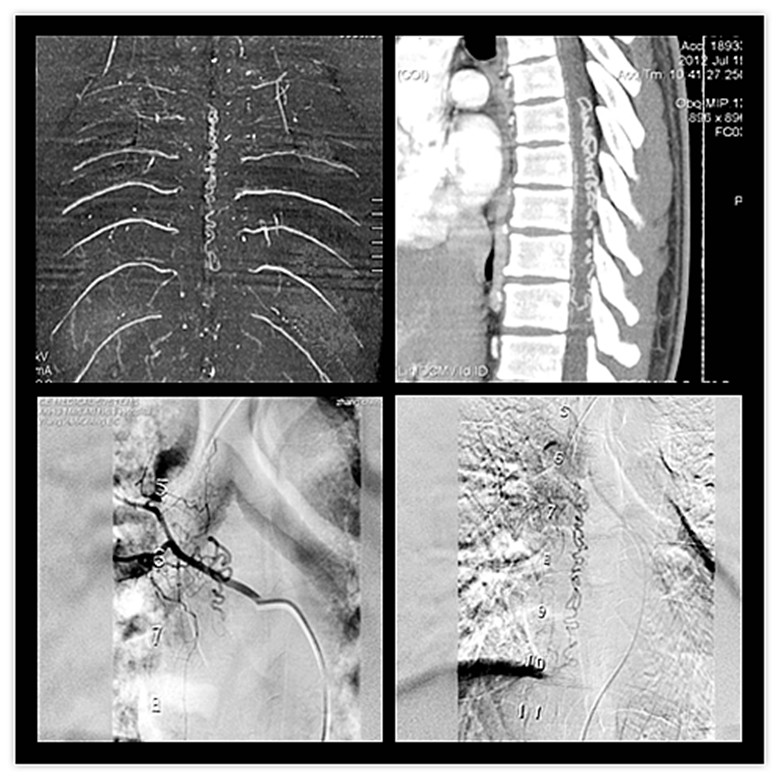

| 前不久,我院放射科通过CT脊髓血管成像(CTA)检查技术成功为一名第一附院转诊的患者明确病因,为神经外科手术提供准确治疗依据。患者男性,35岁,双下肢疼痛并肌力减退,MRI检查考虑脊髓血管性病变。在放射科进行CT扫描后经过MPR及VR后处理,发现椎后静脉明显迂曲扩张改变,找到供血的肋间动脉的前髓动脉供血支,明确诊断为“椎管内硬脊膜下动静脉畸形(SDAVF)”。该病人最近在一附院神经外科施行了手术,术后诊断“SDAVF”。  (图为该患者脊髓CTA扫描和DSA检查影像资料,T5-T10间可见扩张迂曲的畸形血管。) 脊髓血管畸形是一种较少见的先天性疾病。分为动脉型、静脉型和动静脉型三种,其中绝大部分是动静脉畸形,其次为脊髓内海绵状血管瘤。该病可能导致出血和(或)血栓、血管分流引起的缺血、脊髓受压等一系列临床症状。一旦出现并发症预后很差,因而早期诊断和早期治疗十分重要。

脊髓血管畸形的诊断,除病史、体征外,主要依靠影像学。近年来随着MSCT技术的发展,对病变有了更全面的认识。MSCT因其扫描速度快,范围广,有较高的空间和时间分辨率,使CT脊髓血管造影(脊髓CTA)成为可能。脊髓CTA将CT增强技术与薄层、大范围、快速扫描技术相结合,通过合理的后处理,清晰显示脊髓各阶段血管细节,具有无创和操作简便的特点,对于血管变异、血管疾病以及显示病变和血管关系具有重要的价值。